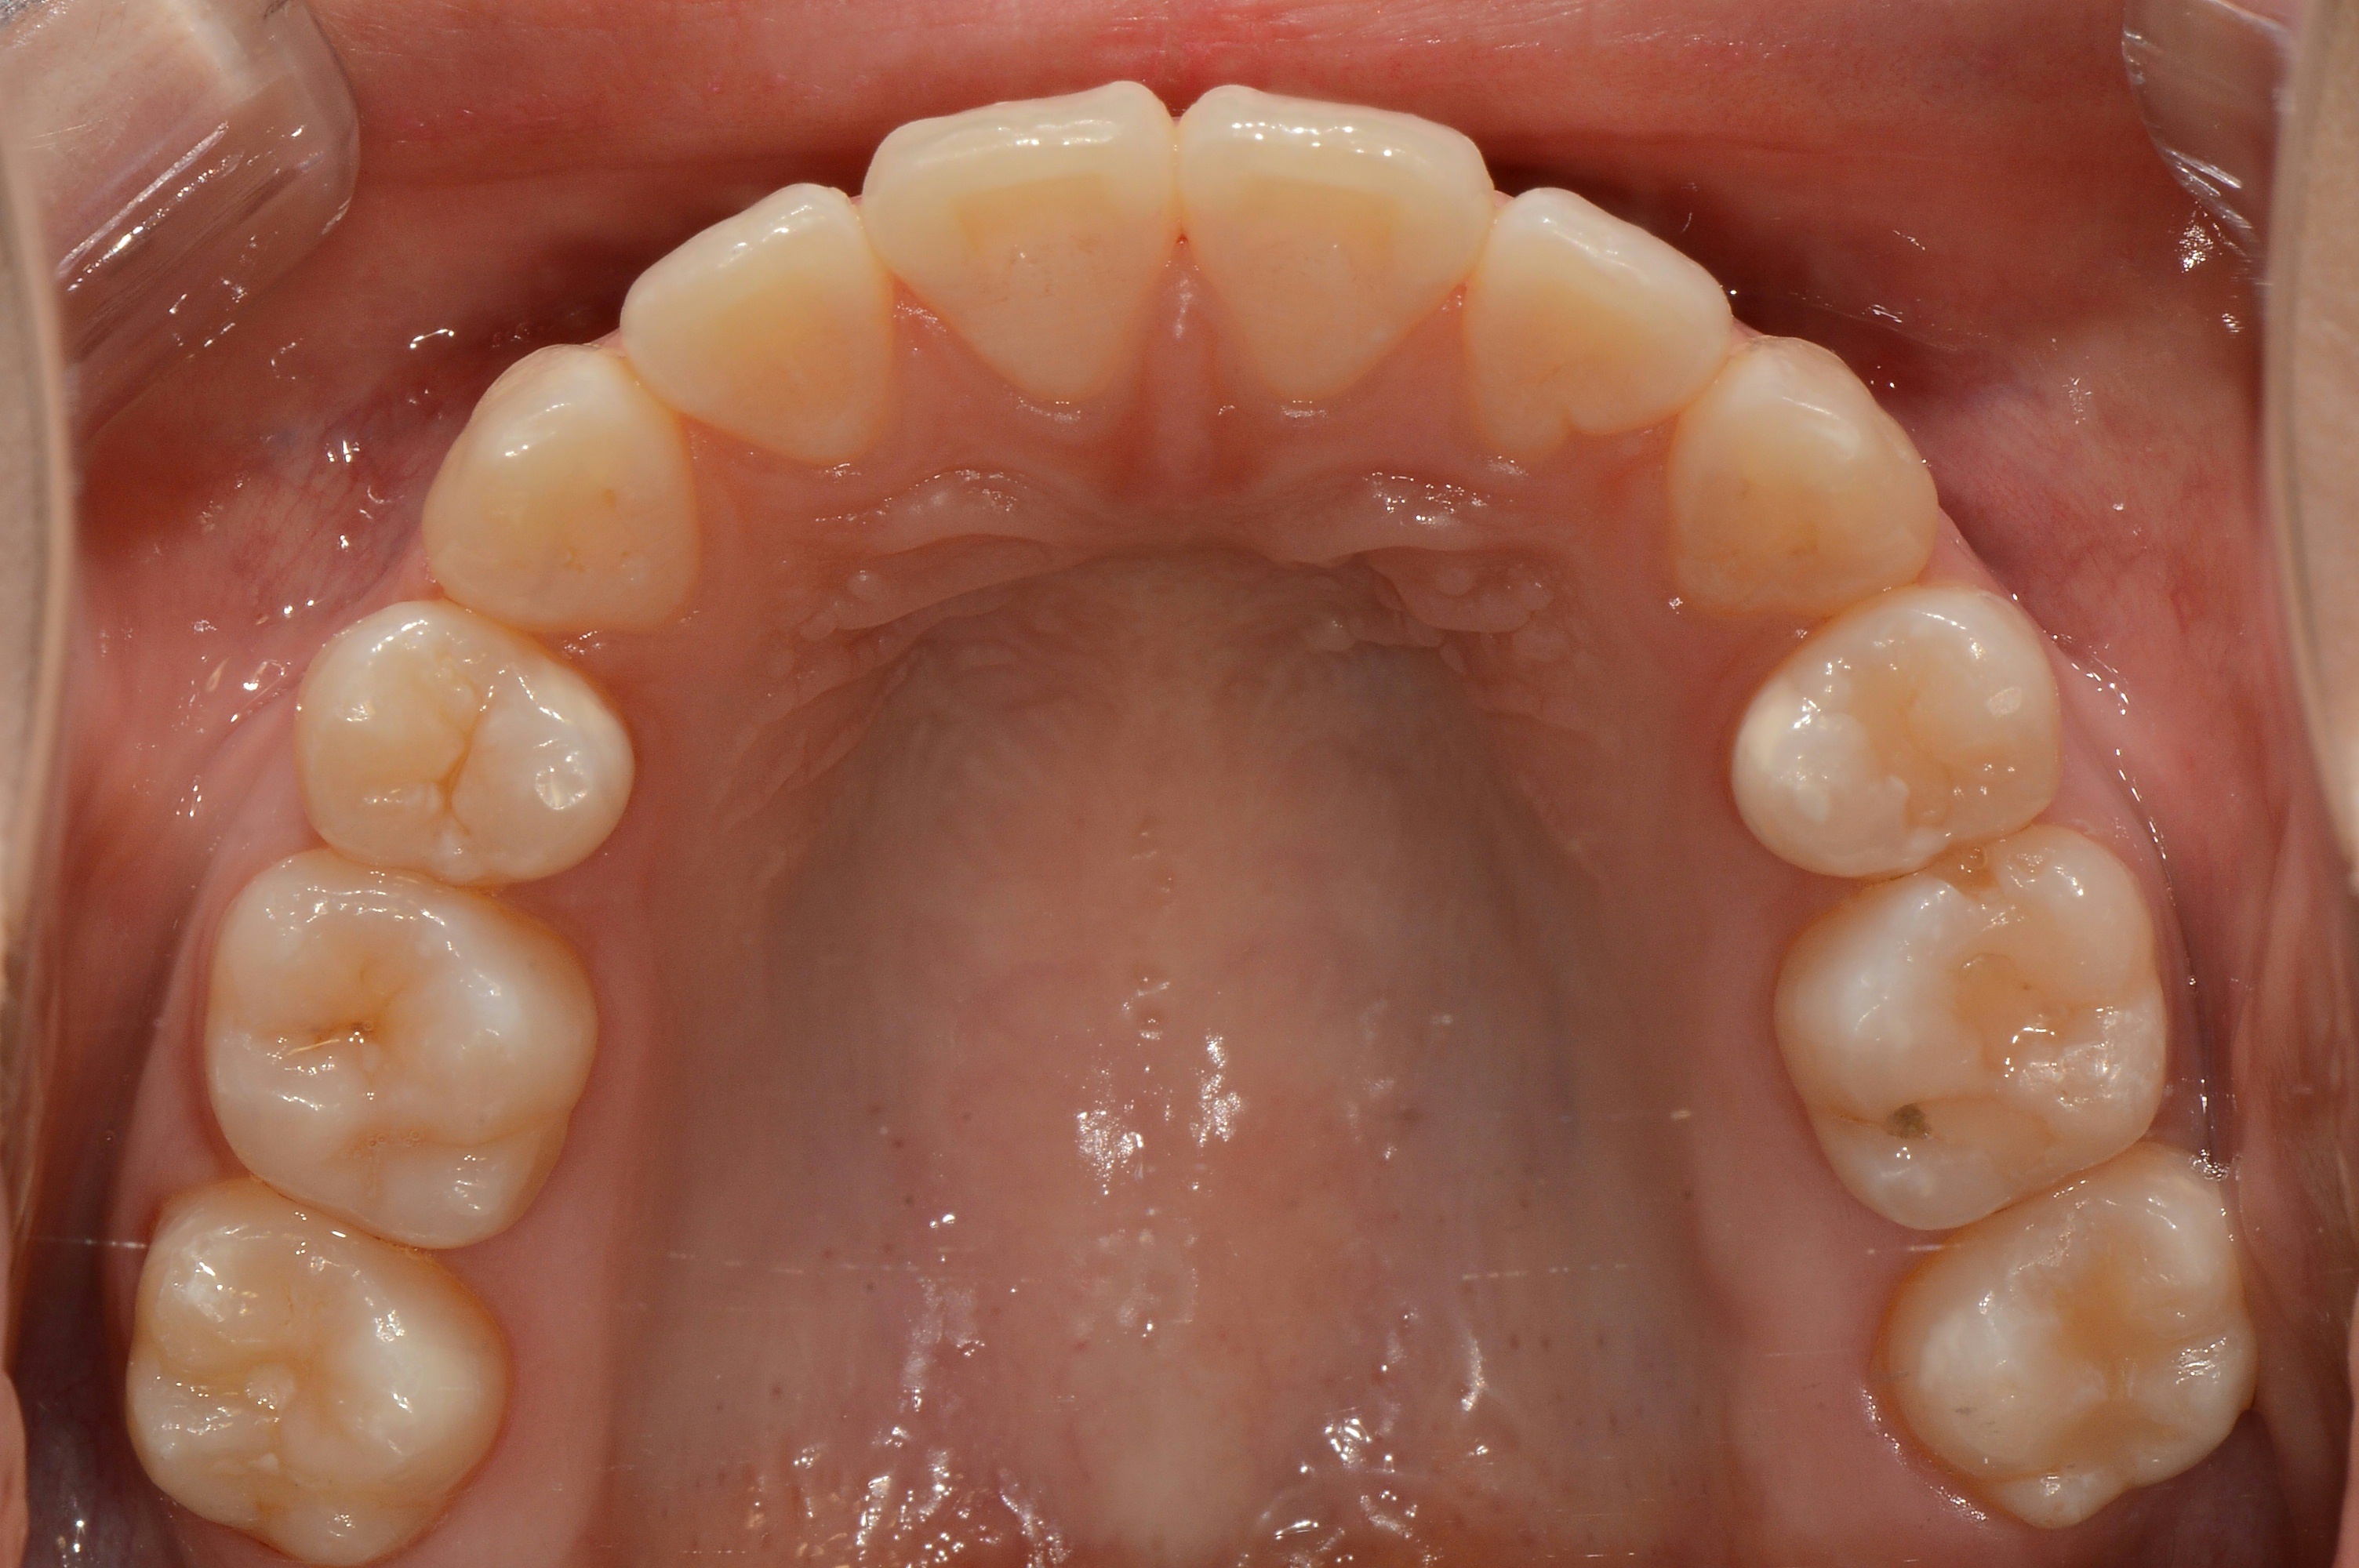

치료 전 사진입니다.